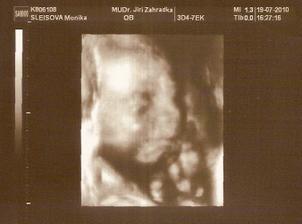

11.5. NT screening, jsem 13+5 a teď čekáme.....12.5. výsledky jsou v normě! 🙂